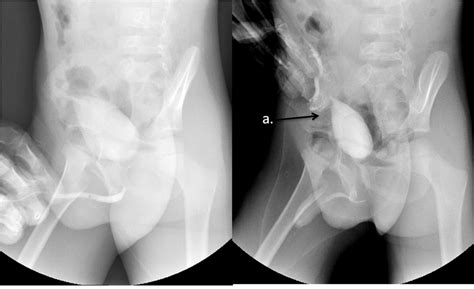

So, you think you might have cellulitis cruris ? The good news is that doctors can usually diagnose it pretty straightforwardly, but they’ll want to be sure. The first thing they’ll do is take a detailed medical history and perform a physical examination . They’ll ask you about your symptoms – when they started, how they’ve progressed, if you have any other health conditions, and if you’ve had any recent injuries or skin breaks. During the physical exam, they’ll look closely at the affected area on your leg. They’ll check for that characteristic redness, swelling, warmth, and tenderness. They’ll also want to see if there are any blisters, streaks, or signs of pus. They might gently press on the area to assess the pain and check for any pus discharge. To confirm the diagnosis and identify the specific bacteria , especially if the infection is severe, recurrent, or not responding to initial treatment, your doctor might order a few tests. A blood test can help check for signs of infection in your body, like an elevated white blood cell count, and can sometimes help identify the bacteria causing the infection. If there’s pus or fluid from a blister or wound, a wound culture might be taken. This involves swabbing the area or collecting fluid and sending it to a lab to grow the bacteria and determine which antibiotic will be most effective. In some cases, particularly if the infection is deep or spreading rapidly, a biopsy of the skin tissue might be considered, but this is less common for typical cellulitis. Imaging tests , like an ultrasound or CT scan, are rarely needed for standard cellulitis but might be used if doctors suspect a deeper infection, such as an abscess or osteomyelitis (bone infection). The goal is to differentiate cellulitis from other conditions that can look similar, like deep vein thrombosis (DVT), an allergic reaction, or even certain types of skin cancer. Your doctor’s experience and the classic presentation of symptoms are often enough for a diagnosis, but these tests provide valuable backup when needed. So, rest assured, they have ways to figure out what’s going on and get you on the path to recovery. It’s all about pinpointing the problem so they can apply the right solution, guys.